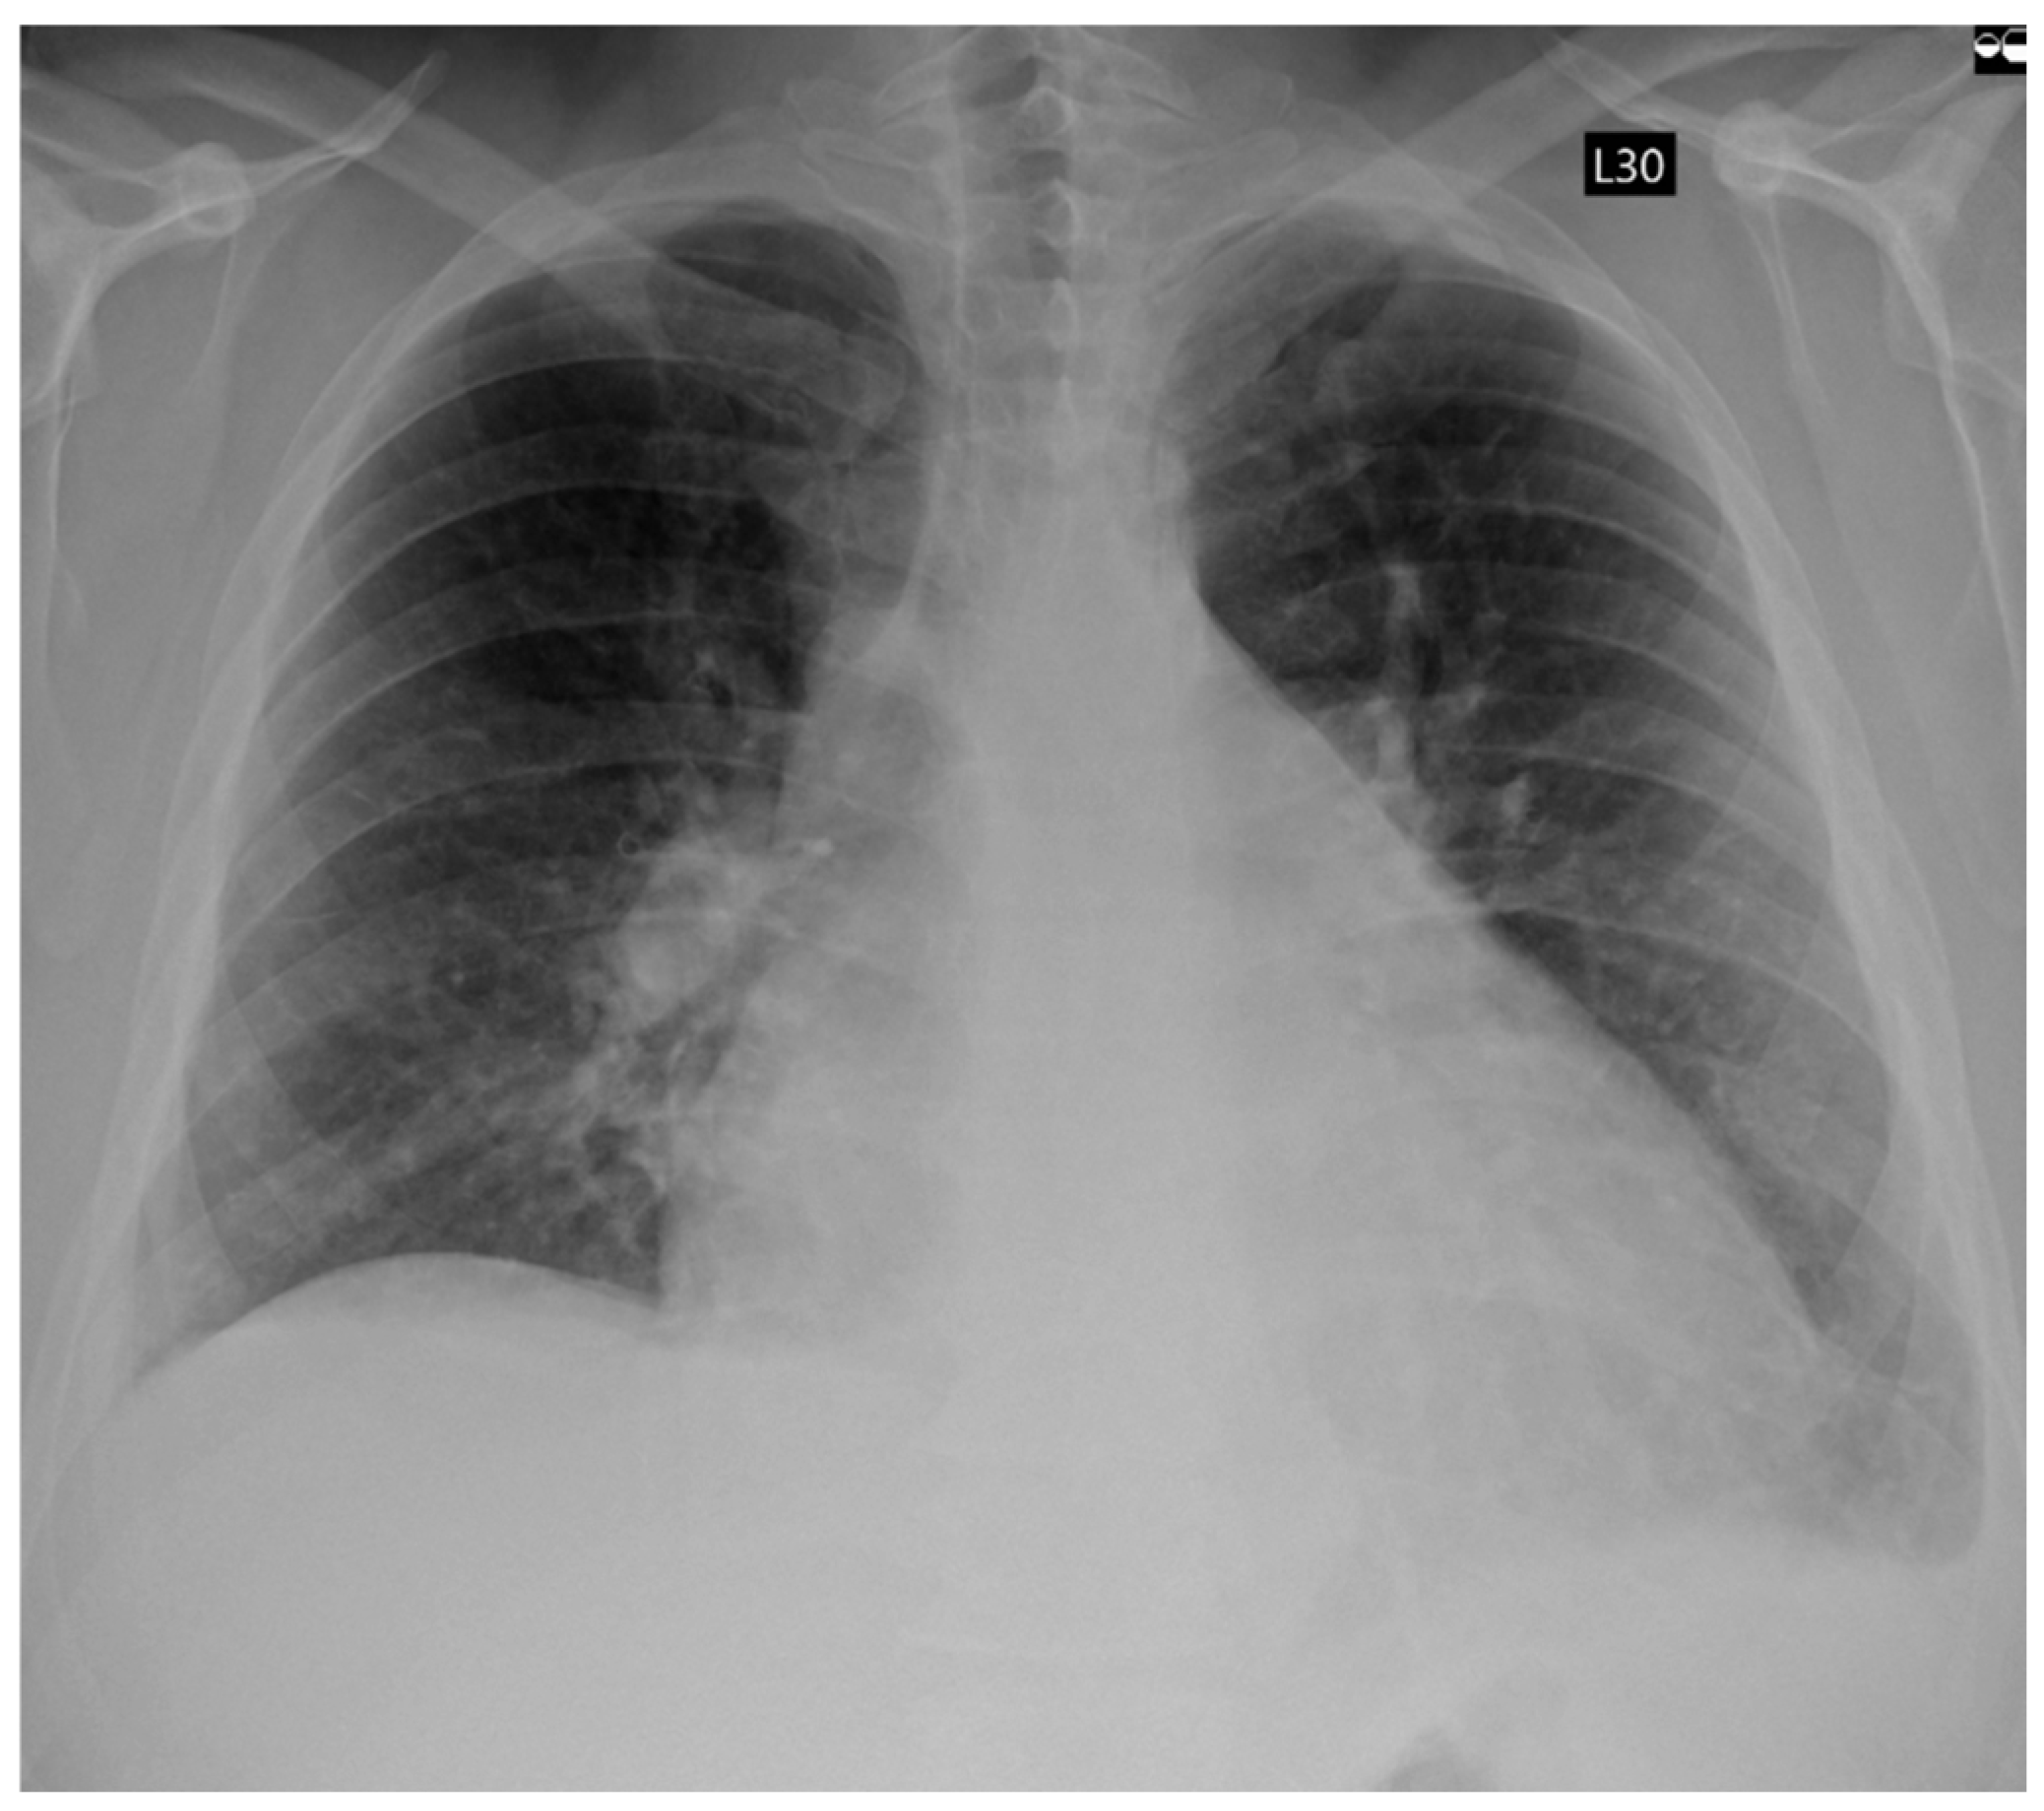

| Echocardiographic Parameters | First Admission | Ablation | Follow-Up |

|---|---|---|---|

| LVEF (%) | 25 | 27 | 54 |

| LVEDD (mm) | 61 | 74 | 63 |

| LVESD (mm) | 55 | 61 | 45 |

| LA (mm) | 48 | 54 | 45 |